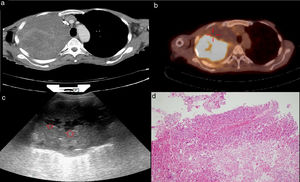

There were 79 (76%) patients in the US-TFNAB diagnostic group and 25 (24%) in the US-TFNAB non-diagnostic group. When the final diagnostic methods of these 25 patients (US-TFNAB non-diagnostic group) were examined, it was observed that 13 (52%) patients’ final diagnosis was achieved using CT-guided Tru-cut biopsies, 9 (36%) with fiberoptic bronchoscopy (FOB), and 3 (12%) with thoracic US-guided Tru-cut biopsies. The distribution of the final histopathologic diagnoses of the patients is given in Table 3. The mean number of TFNABs per patient was 1.09 ± 0.28.When the PET-CT reports of the patients were examined, the mean SUVmax in PET-CT scans was 19.5 ± 10.1 in the US-TFNAB diagnostic group, whereas it was 15.1 ± 8.9 in the US-TFNAB non-diagnostic group (p = 0.016) (Fig. 2). When heterogeneous FDG uptake and homogeneous FDG uptake characteristics in PET-CT of biopsied mass lesions of the patients were examined, heterogeneous FDG uptake was reported in 41 (5) patients in the US-TFNAB diagnostic group and in 16 (64%) patients in the US-TFNAB non-diagnostic group (Figs. 2a–d) (Figs. 3a–d). There was no statistically significant relationship between lesions showing homogeneous or heterogeneous FDG uptake and the diagnostic success of the US guided-TFNAB procedure (p = 0.289) (Table 2).

a) An approximately 15 × 10-cm mass in the right lung in thoracic CT. b) Heterogeneous FDG uptake with observed necrotic areas inside the mass in PET-CT. c) Anechoic necrotic foci in the ultrasonographic image of the same mass. d) Necrotic tissue specimen (HEx200) whose structural and cellular details cannot be evaluated in the histopathologic preparation.

The presence of various ratios of FDG uptake in various areas in PET-CT (heterogeneous FDG uptake) allows differentiation of necrotic areas, granulation tissues, and viable tumor tissues inside tumoral tissue. Clinical trials have shown that PET-CT can better assess proliferative activity in tumoral tissue and is useful in distinguishing viable tumor tissue from fibrotic tissue.27–30 In a study by Cataluna31 that evaluated factors affecting the diagnostic accuracy of bronchial biopsies, the degree of cell differentiation and the absence of necrosis in pathologic specimens were shown to be the most influential factors on diagnostic accuracy. They demonstrated that in the absence of necrosis in a pathology specimen, diagnostic accuracy was 5.2 times higher. Further, Greses et al.32 found diagnostic sensitivity to be 69.6% in their series of 151 patients, and demonstrated that one of the variables that significantly affected diagnostic accuracy in biopsy procedures was the presence of necrosis in the biopsy material. They reported that the diagnostic success was 2.6-times higher when there was no necrosis in the biopsy material. In spite of a higher rate (64%) of patients whose PET-CT revealed heterogeneous uptake due to the presence of a necrotic component than in the US-TFNAB non-diagnostic group, no statistically significant difference was found between the two groups (p = 0.289). As is widely known, US is very sensitive in the differentiation of necrotic areas in tissues.16 Necrotic areas with thoracic US are seen as focal heterogeneous echo-densities within a hypoechoic mass lesion33 (Fig. 3c). We thought that mass lesions with a necrotic component in PET-CT might negatively affect diagnostic success; however, we found no statistically significant relationship. This may be associated with the low number of patients and real-time nature of US-guided TFNABs. In real-time procedures, needle movements can be tracked within the lesion. The direction of the needle can be determined by the operator. Therefore, during biopsy, necrotic regions may be identified and biopsy of those necrotic regions can be avoided.